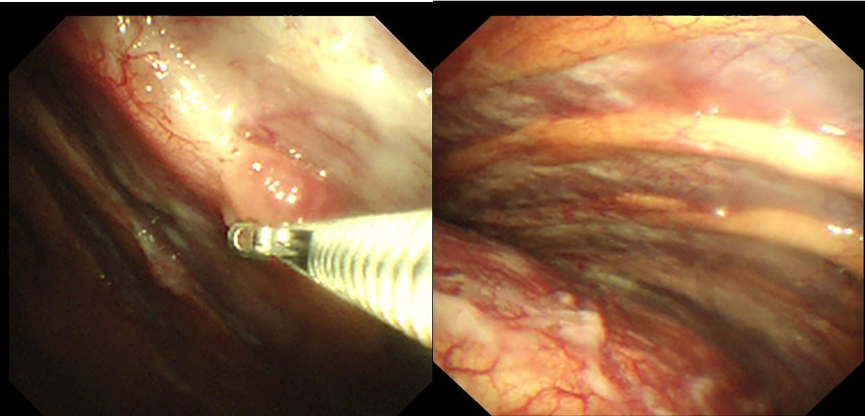

手术当日,患者左侧卧位,采用局麻方式,经超声精准定位后,于右侧腋中线5-6肋间进行人工气胸操作,内科胸腔镜直视下,可观察到壁层胸膜和脏层胸膜,实时活检。既明确诊断,又确认了分期,术后患者恢复良好。

此外,胸腔镜手术属于微创手术,创伤小、恢复快。在治疗气胸、良恶性顽固性胸腔积液胸膜固定术、急性脓胸、血胸、乳糜胸、支气管胸膜瘘、松解胸膜黏连等方面应用广泛。“人工气胸下胸腔镜检查”通过向胸腔内注入气体,人为制造气胸,从而拓展胸腔空间,为胸腔镜的顺利进入和操作创造良好视野条件。胸腔镜犹如医生的透视眼,能够深入胸腔内部,直接观察病变部位的细微形态、色泽等变化,并精准抓取病变组织进行病理检查,在处理复杂肺部疾病诊断时有着独特的优势。这一技术还能降低手术并发症风险,缩短患者住院时间,极大改善患者的就医体验和预后康复情况。